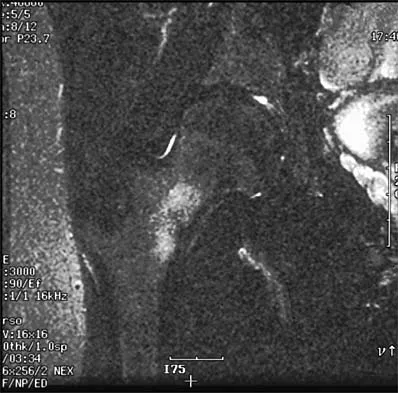

Figure 42 shows the sagittal T2-weighted MRI scan of a patient's right knee. These findings are most commonly seen with a complete tear of the

The MRI scan reveals disruption of the lateral capsule and ligaments with fluid in the soft tissues laterally. Additionally, there is a large bone bruise on the medial femoral condyle. This combination indicates injury to the posterolateral complex. These injuries often have coexisting anterior and/or posterior cruciate ligament injuries. Failure to recognize the posterolateral corner injury can lead to failure of anterior or posterior cruciate ligament reconstructions. LaPrade RF, Gilbert TJ, Bollom TS, et al: The magnetic resonance imaging appearance of individual structures of the posterolateral knee: A prospective study of normal knees and knees with surgically verified grade III injuries. Am J Sports Med 2000;28:191-199.